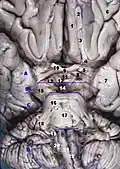

![]() Перпендикулярный разрез ствола мозга человека на уровне верхних холмиков четверохолмия, показывающий путь глазодвигательного нерва. Межножковая ямка не отмечена, но хорошо видна внизу в центре. | |

Межножковая ямка — приблизительно ромбовидной формы заполненная спинномозговой жидкостью полость в основании мозга, омывающая снизу ликвором ряд базальных структур головного мозга. Спереди межножковая ямка ограничена перекрёстом зрительных нервов, сзади — передне-верхней поверхностью варолиева моста, с передне-боковых поверхностей — постепенно сходящимися впереди в перекрёсте зрительных нервов зрительными трактами, а с задне-боковых поверхностей — постепенно расходящимися ножками мозга.

Структуры головного мозга, омываемые снизу ликвором в межножковой ямке, в порядке перечисления от задней оконечности межножковой ямки к передней, включают в себя заднее продырявленное вещество, сосцевидные тельца и серый бугор гипоталамуса, ножку гипофиза, а также сам гипофиз.